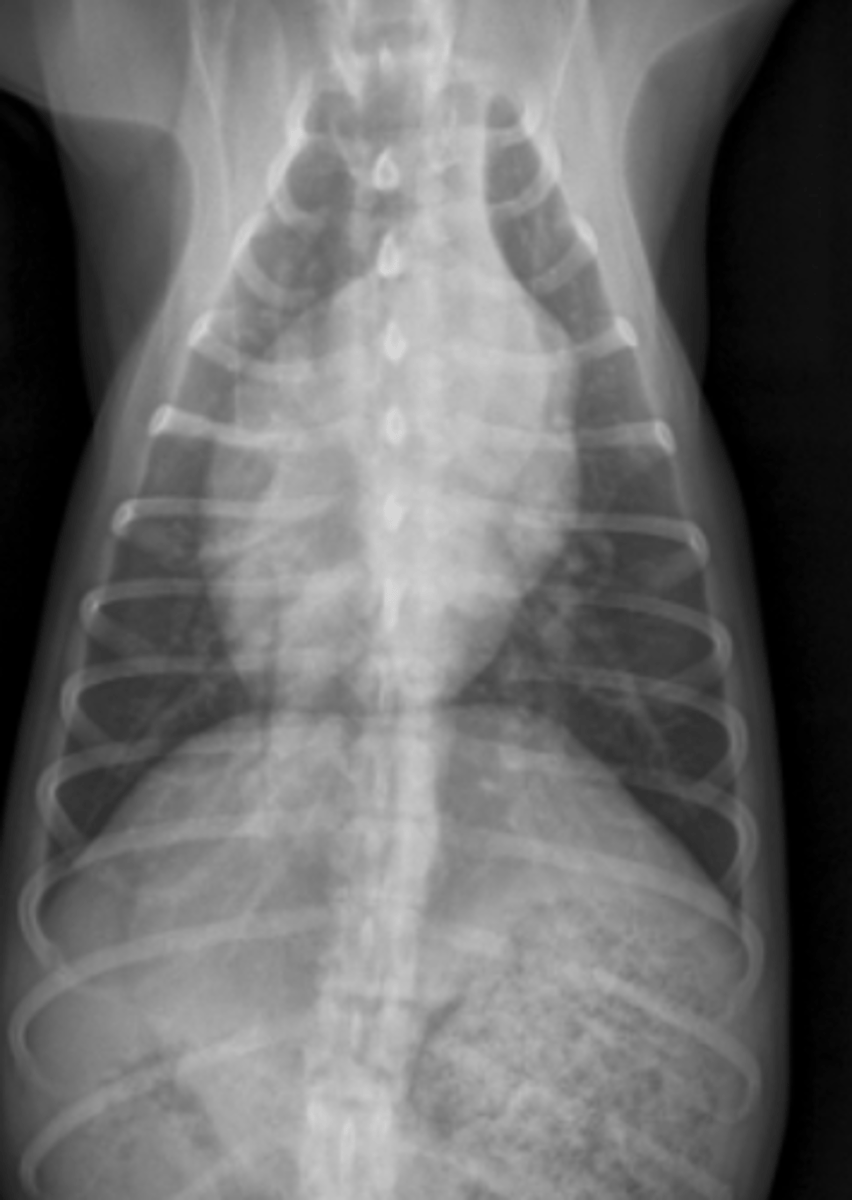

microcardias

(silueta separado de la diafragma)

patología:

(silueta separado del esternón)